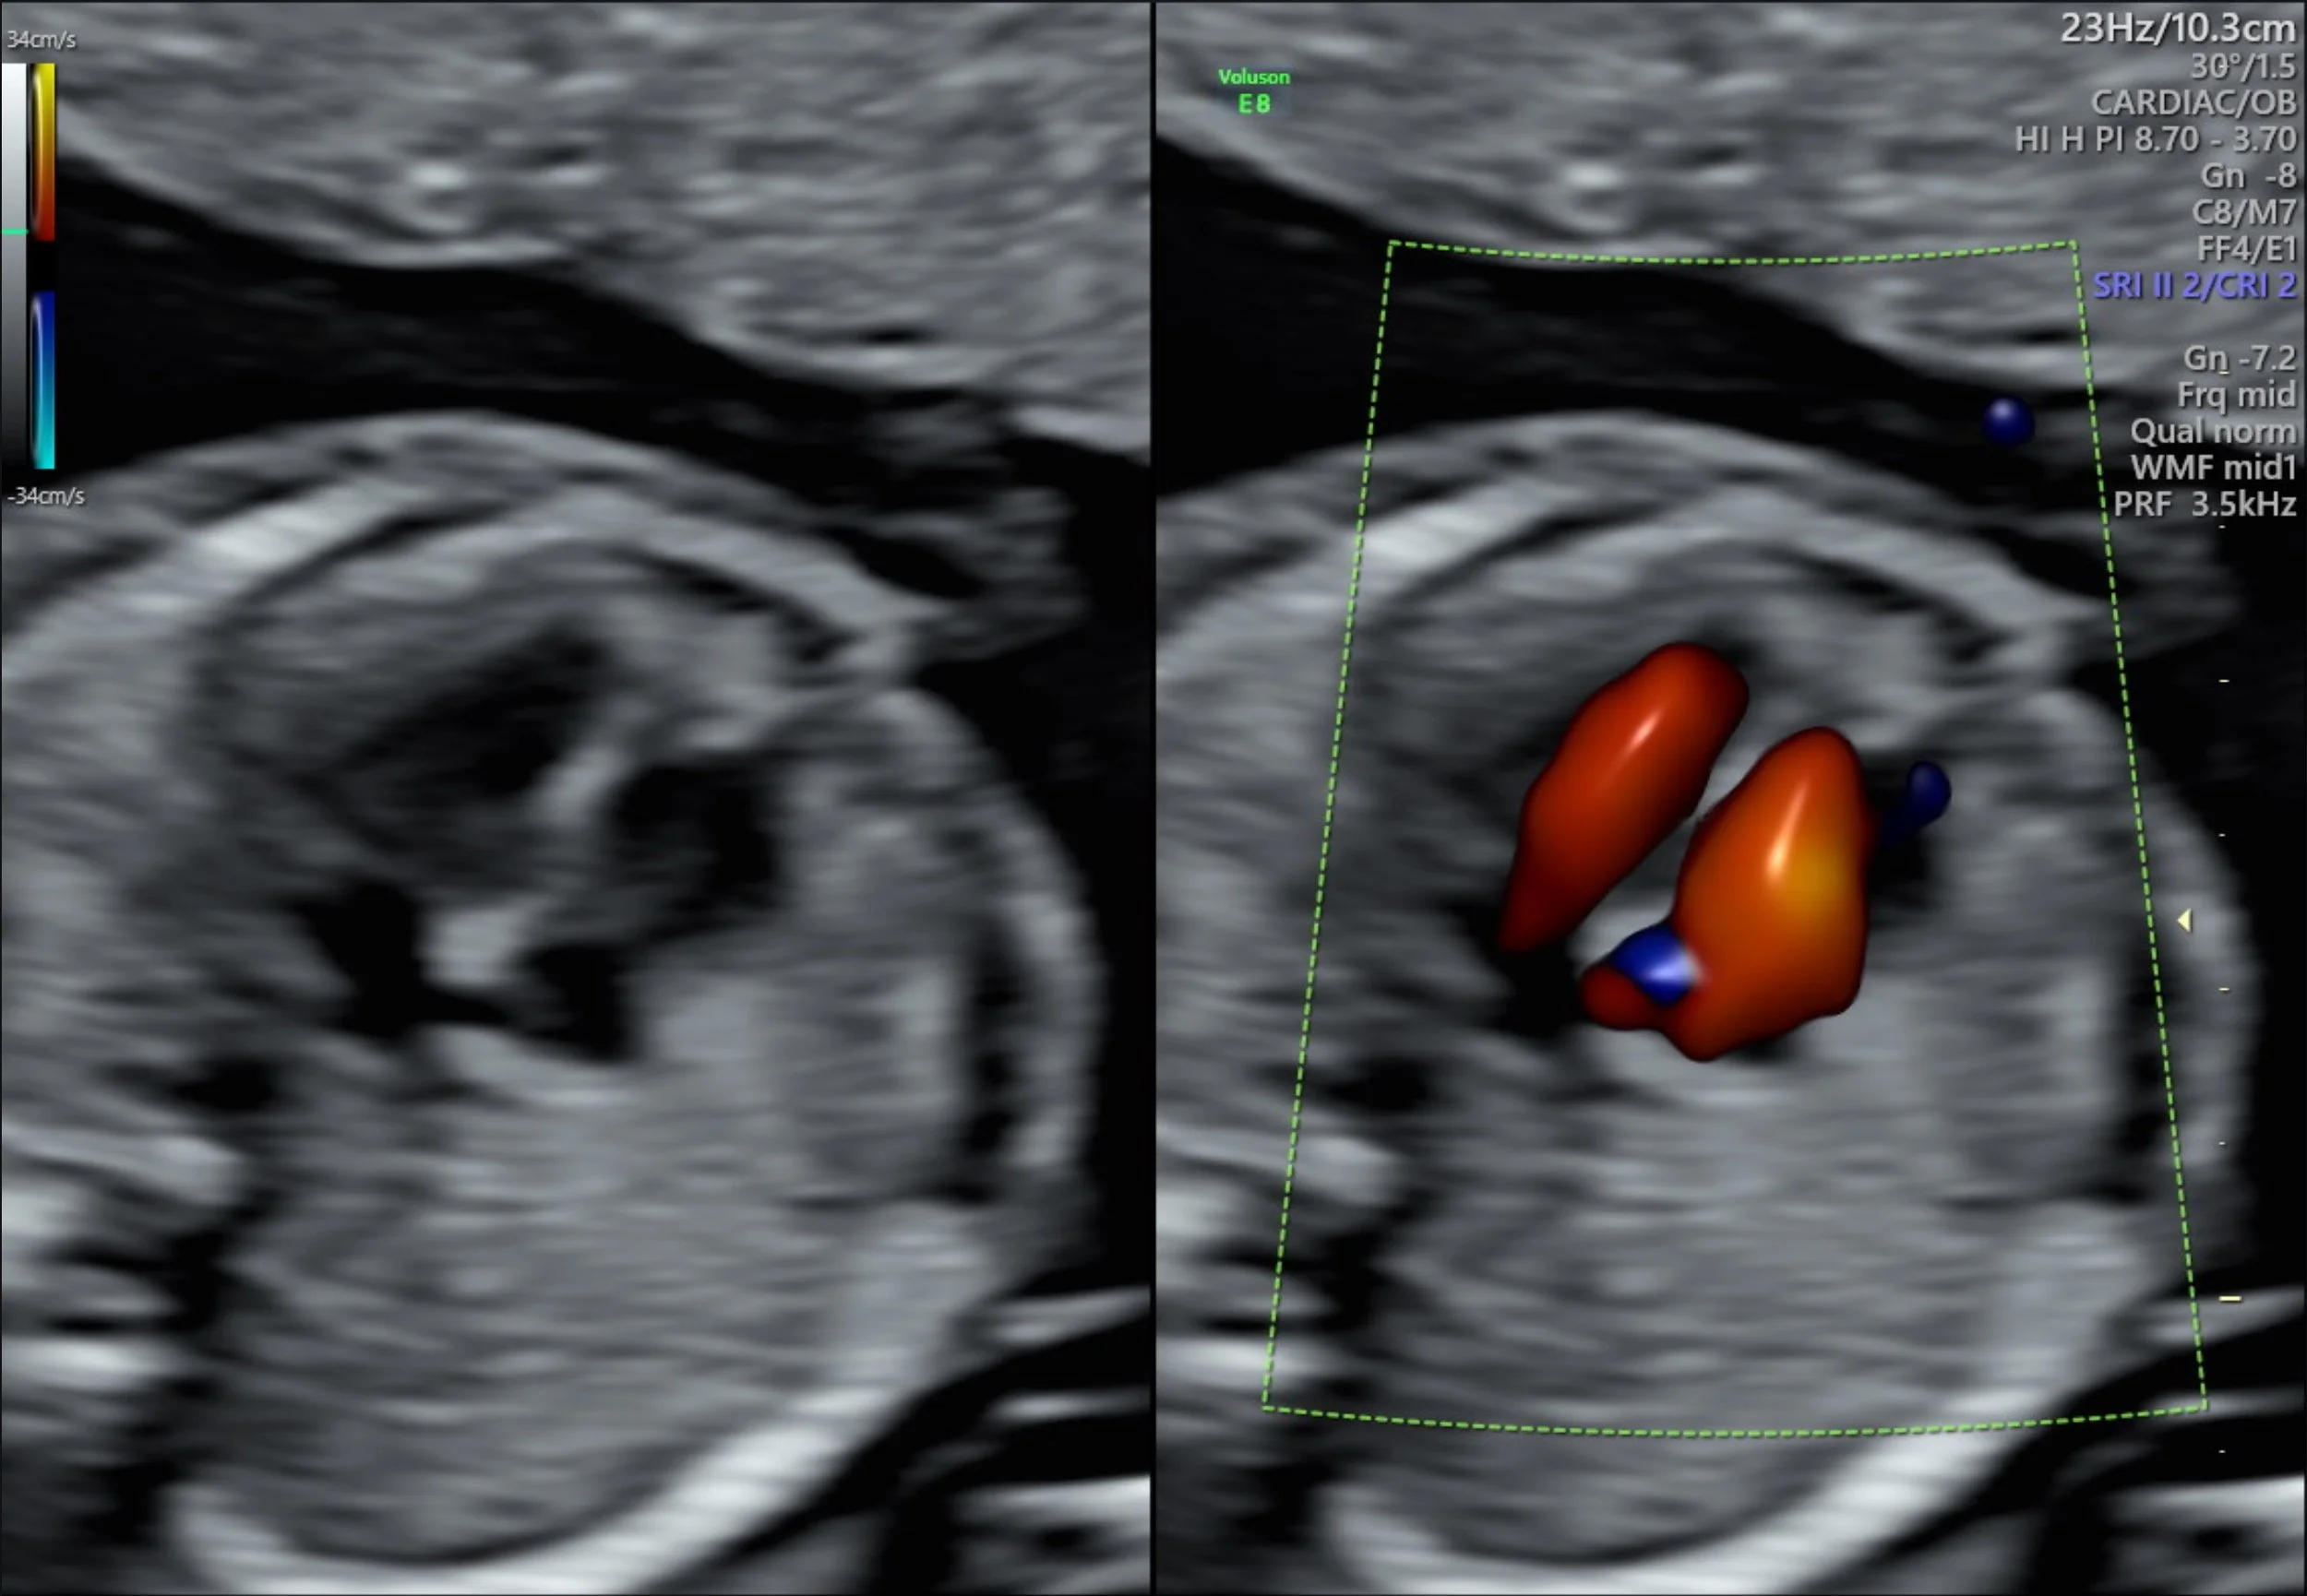

- Perform a early detailed screening of the developmental anatomy of the fetus’ head, brain, face, palate, heart, diaphragm, lungs, kidneys, abdominal wall, bladder, spine, skin line, arms, hands, legs and feet.

For the best results, we recommend scheduling your appointment as early in your pregnancy as possible to ensure that the procedure can be performed during the optimal timeframe. Use our Pregnancy Scan Calculator to determine the most suitable dates for your scan. At Trinity Imaging we conducte Early Anatomy Scans from 16 weeks as our experienced sonographers have found that this specific timeframe allows for optimal visualization of your baby's development, including intricate structures such as the brain, heart, and kidneys. This small window of time can make a significant difference in the clarity and detail of the scan, providing valuable insights into your baby's well-being.